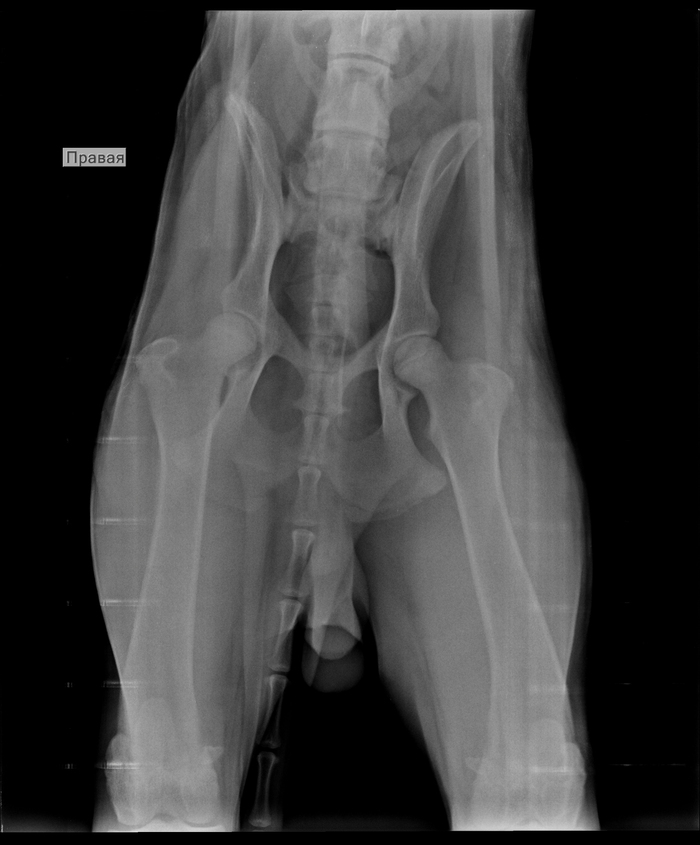

А это собака с переломом позвоночника. Если ей обеспечить должный уход, она будет в режиме счастливой дурилки. Но да, лишь при должном уходе, иначе все обернется смертью от застоя мочи, цистита, почечной недостаточности, ну и дерматиты вдогонку.

А еще я лично знаю как минимум нескольких животных с переломом позвоночника, которым удалось выработать спинальную походку, благодаря стараниям владельцев, и в итоге владельцы просто следят за их мочеиспусканием и дефекацией, помогая опорожнить мочевой пузырь мануально, а животные радуются жизни и радуют владельцев.